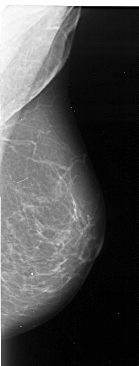

A_1102_1.LEFT_MLO

LEFT_MLO LINES 5236 PIXELS_PER_LINE 2401 BITS_PER_PIXEL 16 RESOLUTION 42 OVERLAY